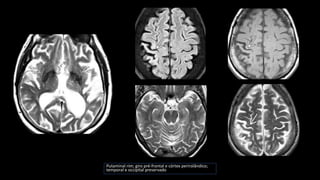

Degeneração corticobasal

• Inclusões TAU em neurônios e na glia

• Atrofia frontotemporal assimétrica

• Áreas motoras e sensoriais

• Preservação do occipital e parietal

• Atrofia e despigmentação da substância nigra

• “alien limb phenomenon”

• Sintomas parkinsoninsmo não respondem ao Levodopa

• Distúrbios cognitivos, linguagem (afasia não fluente)

Putaminal rim; giro pré-frontal e córtex perirolândico;

temporal e occipital preservado